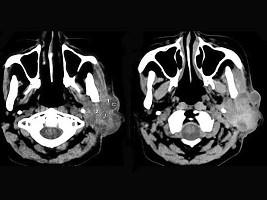

问题 女,55岁,鼻咽癌放疗15年,近一周左耳根部肿胀,无发热,PE:左耳根部皮下扪及三个结节,有波动感和轻压痛,CT如图所示,最可能的诊断是 ( )

选项 A、左腮腺恶性混合瘤 B、左腮腺蜂窝织炎 C、左腮腺混合瘤 D、左腮腺腺淋巴瘤 E、左腮腺腺瘤

答案 B